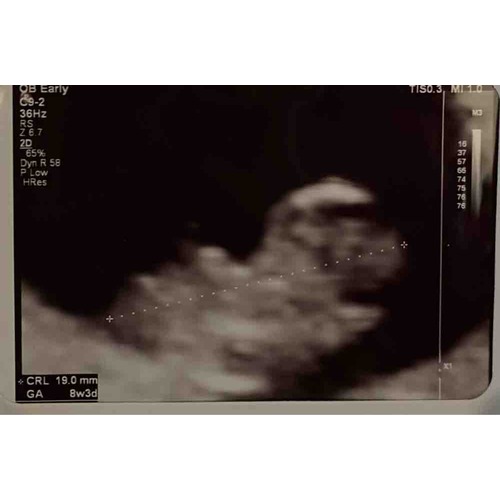

Echo van vandaag 8+2